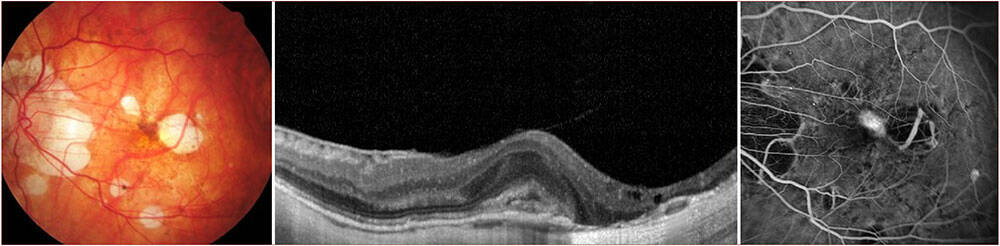

Figure 2. Patiente de 26 ans présentant une baisse d’acuité visuelle avec un décollement séreux rétinien hémorragique visible à l’OCT (A, tête de flèche). Les temps tardifs de l’angiographie à la fluorescéine ne montrent aucune diffusion (B) et la rupture de la membrane de Bruch est hypofluorescente sur le temps tardif de l’angiographie au vert d’indocyanine (C). L’OCT-A segmentée sur la rétine externe ne montre aucun signal vasculaire (D).